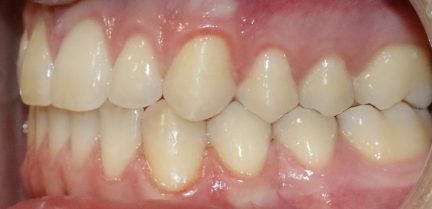

Classe III, articulé croisé postérieur, articulé croisé antérieur, occlusion bout-à-bout, articulation ouverte, arcades étroites, arcades asymétriques, déviation médiane maxillaire, déviation médiane mandibulaire, décalage médian, chevauchement, rotations

État initial